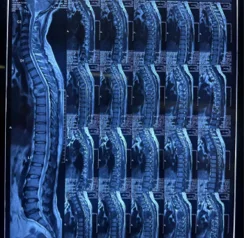

Before & After Clinical Gallery

We showcase real patient cases (with consent), including:

- Pre- and Post-operative MRIs and X-rays

- Disc Herniations, Stenosis, and Spondylolisthesis cases

- Visible improvement in alignment and decompression